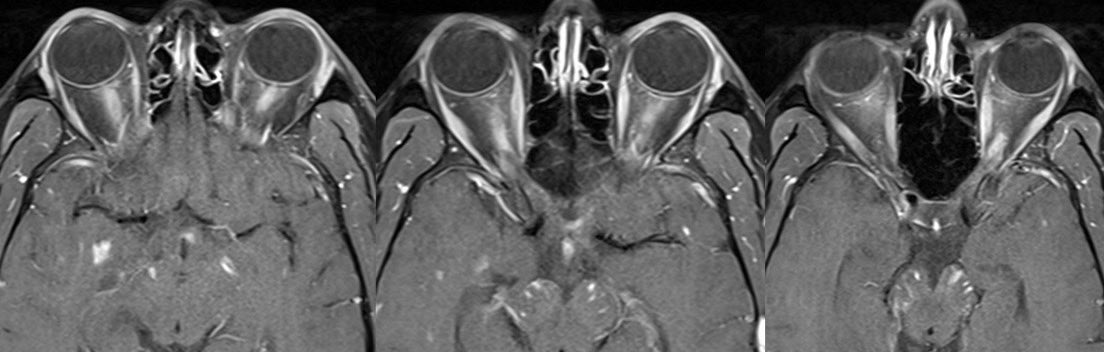

▶️OPTIC NERVES: Long segment BILATERAL edematous & tortuous optic nerves predominantly involving the ANTERIOR nerves x.com